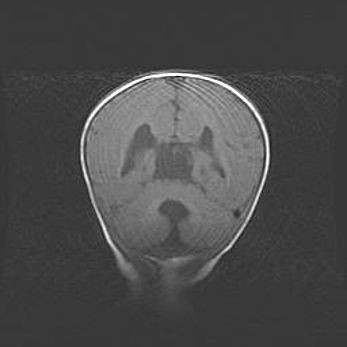

Наружная гидроцефалия с возможной атрофией височных областей.

Возраст: 28 дней

Вес: 3670 г

Пол: мужской

Окружность головы: 38 см

Срок гестации: 40 недель

Гидроцефалия головного мозга у новорожденных – это заболевание, которое характеризуется скоплением избыточного количества спинномозговой жидкости в желудочковой системе головного мозга в результате затруднения её перемещения от места выработки к месту поглощения в кровеносную систему или вследствие нарушения абсорбции. При открытой наружной форме гидроцефалии у новорожденных расширяются и переполняются субарахноидные пространства.

При нормотензивных  формах,  которые,  как  правило,  являются  следствием  перенесенных ишемических  повреждений  паренхимы  мозга,  возможно  сочетание микроцефалии  с нормотензивной гидроцефалией. В основе данных изменений лежит атрофия больших полушарий с преимущественной  локализацией  в  лобно-височных  областях.